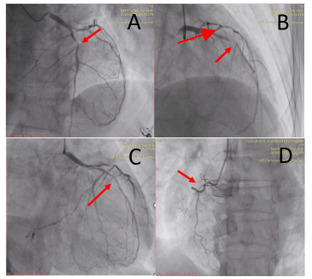

Hình 2. Kết quả chụp động mạch vành: hẹp 50–60% đoạn xa thân chung, hẹp khít 99% động mạch liên thất trước đoạn gần (LAD) (mũi tên hình A và B), hẹp 70–80% động mạch mũ (LCx) và tắc mạn tính động mạch vành phải (RCA) (mũi tên hình D).

Với kết quả trên, bệnh nhân có chỉ định can thiệp cấp cứu LAD, can thiệp trì hoãn RCA.